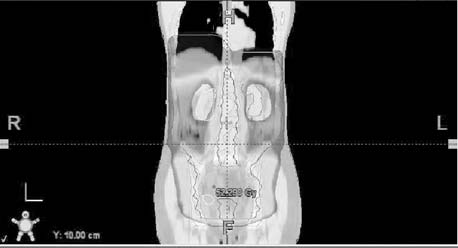

Obr. č. 1: Distribuce izodóz při abdominopelvickém

ozáření - technice „open field" v rovině transverzální, při

frontální a sagitální rekonstrukci, 3D